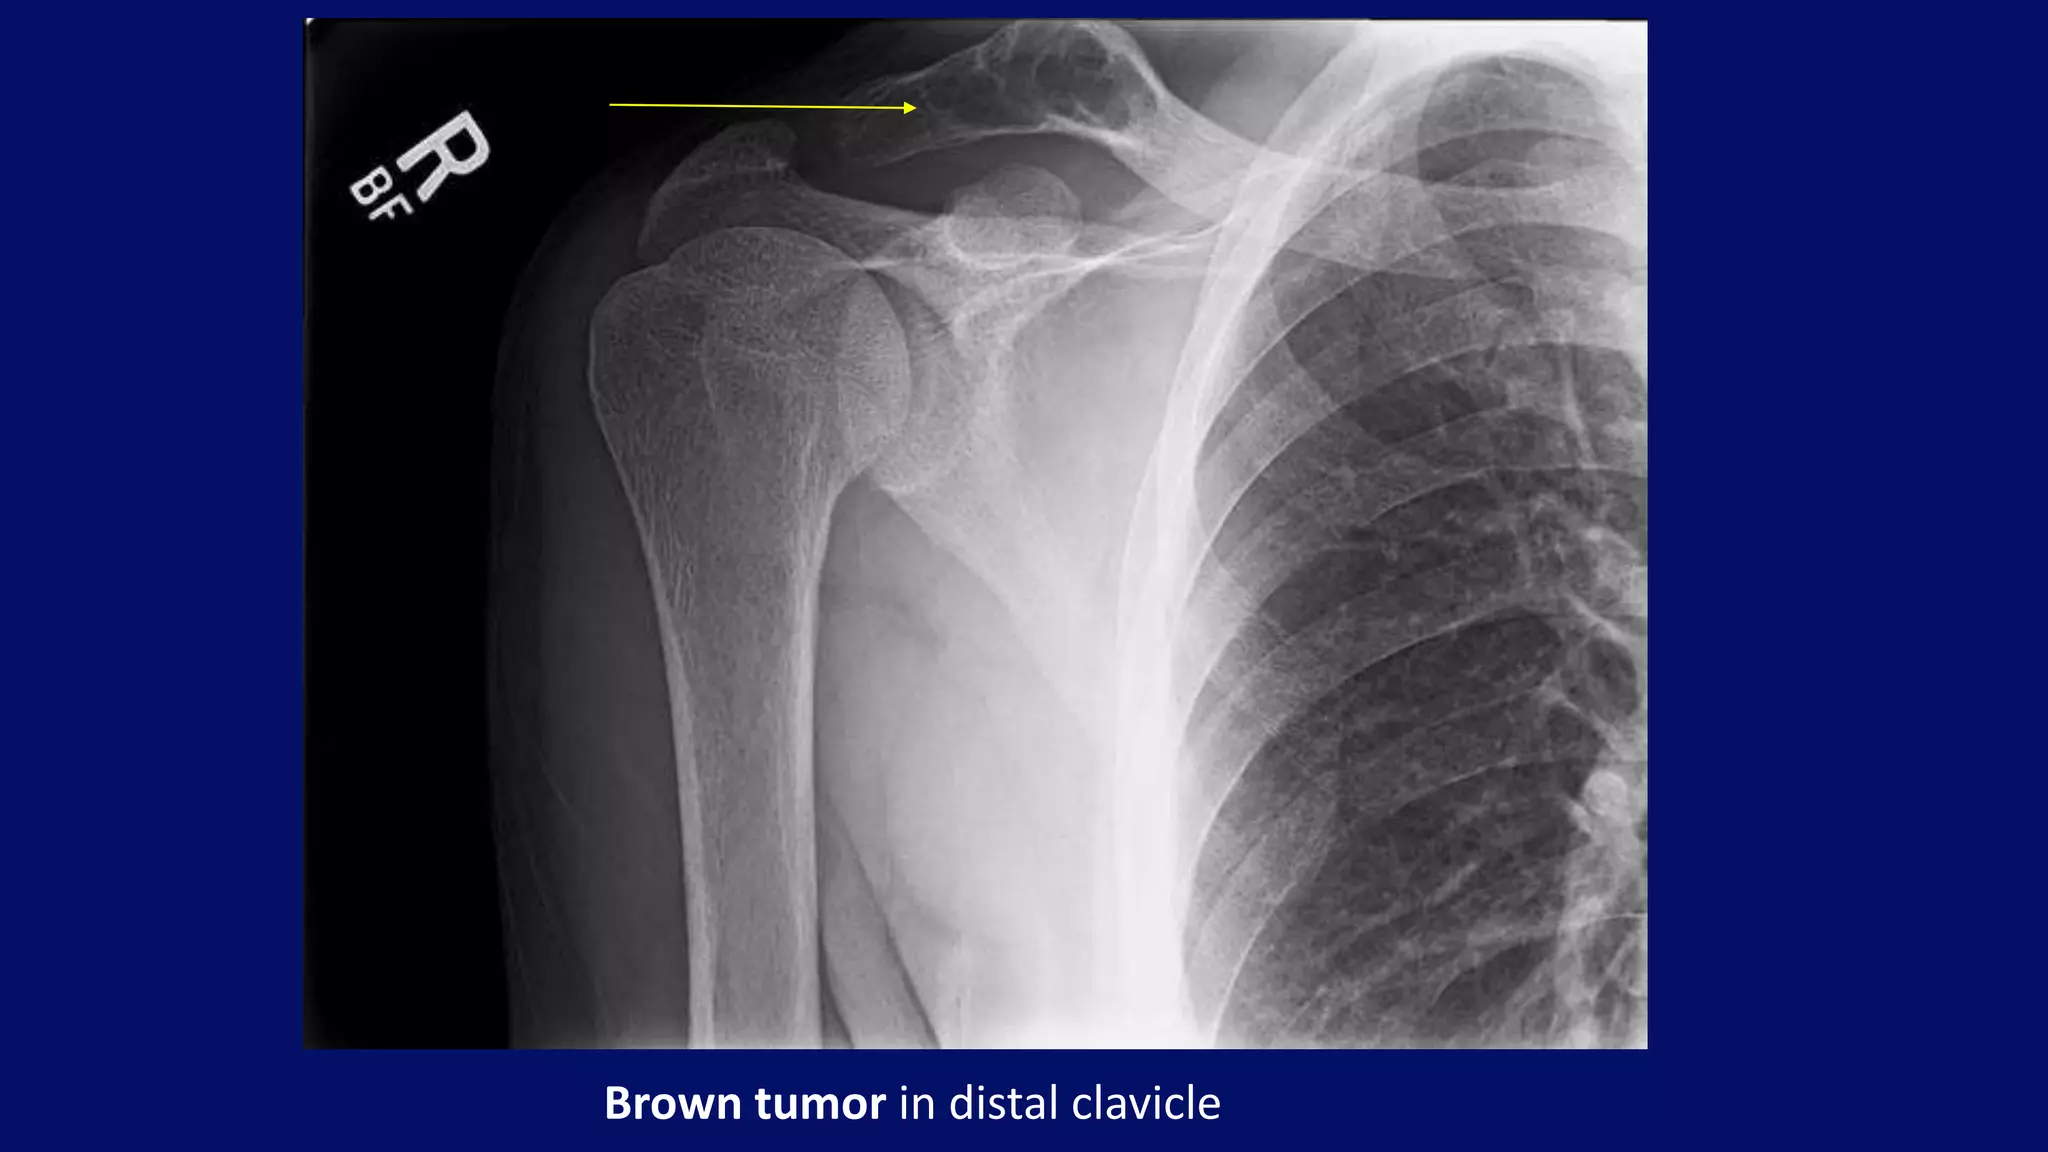

Brown tumor in distal clavicle

• #104 A brown tumour (also known as osteitis fibrosa cystica or rarely osteoclastoma) is one of the manifestations of hyperparathyroidism. It represents a reparative cellular process, rather than a neoplastic process. Plain film Well-defined, purely lytic lesions that provoke little reactive bone. The cortex may be thinned and expanded, but will not be penetrated. A well-defined, mildly expansile lesion is observed in the distal clavicle approximately 1cm proximal to the distal articular surface. The lesion is soap-bubbly in appearance with mild cortical thinning. There is no evidence of cortical violation or overlying periosteal reaction.  Overall bone density appears moderately diminished. The acromioclavicular joint appears widened, with an indistinct distal clavicular articular surface. The cortex along the medial aspect of the humeral neck appears thinned and feathery on the external rotation view.